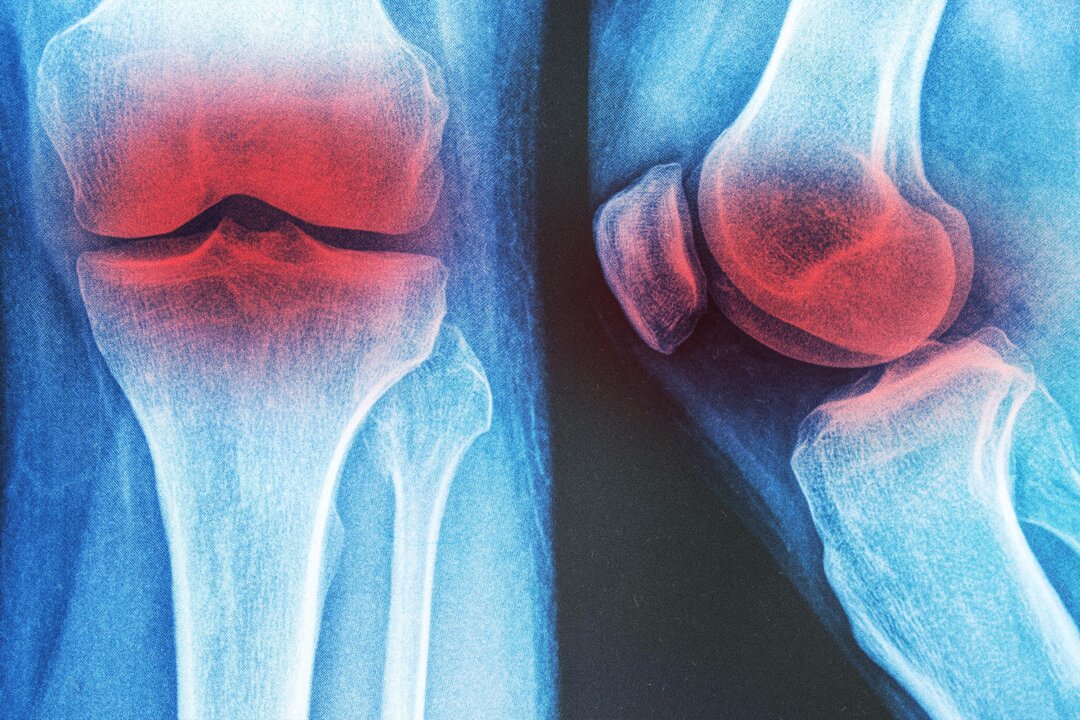

Physiotherapist Alex Lee had a 64-year-old patient with knee arthritis. She experienced difficulty walking for more than 10 minutes at a time because of pain. Her stiff knee joints and weak leg muscles made her afraid of falling.

Approximately 10 percent of men and 13 percent of women older than 60 have knee arthritis, a condition associated with pain and disability.